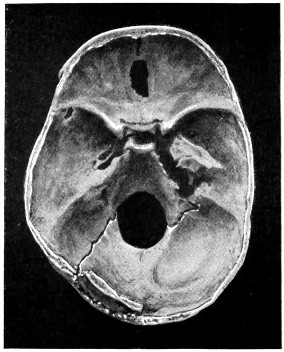

29 A and B. The base of the skull and the base as seen on transillumination 70, 71

30. Plan of the base of the skull 77

50 A and B. The inner aspect of the skull and the same seen on transillumination 137